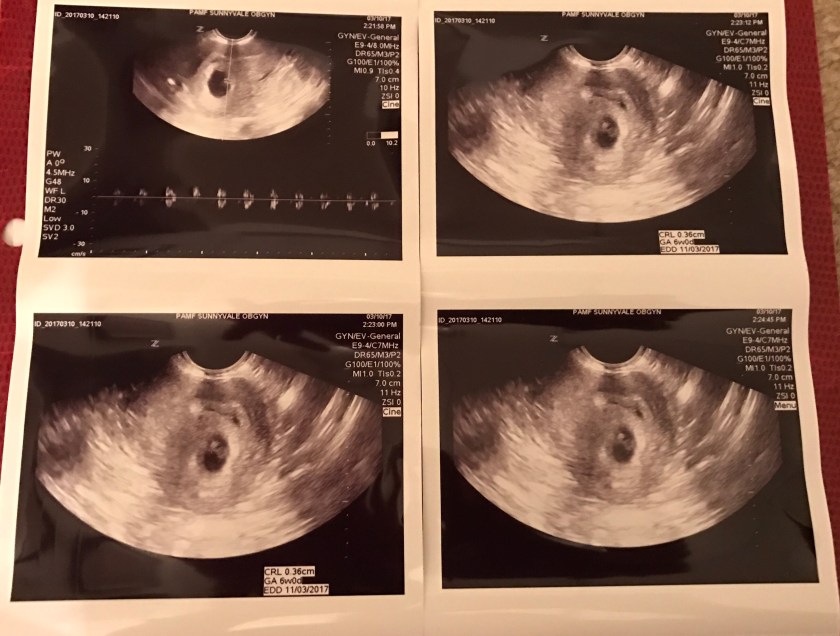

Yesterday Matt, Candy and I went to my 23 week check up with Dr. G. In this appointment, like the one before it he did not take any sonograms, so in this blog entry I will include some of my favorite sonograms so far. This was the first series of ones we received, looking at them even now I still can’t make out a lot of the structures I knew he saw but it was so great to have them. We didn’t even realize at the time that not all babies at 6 week will show a fetal pole heartbeat (and can still be normal and healthy), so we were very lucky to have the sound confirmation so soon in my pregnancy.